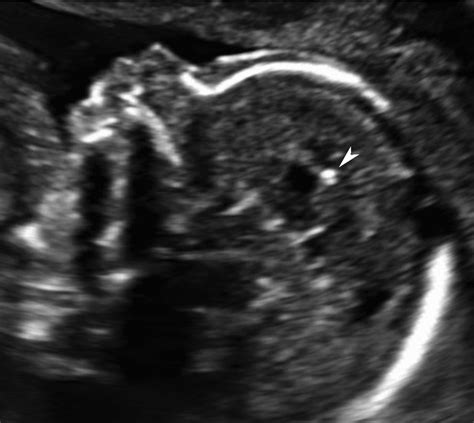

These deposits appear as bright, white spots on an ultrasound, often referred to as "echogenic foci." The medical significance of these spots depends entirely on where they are located and whether they are associated with other abnormalities. In many cases, these calcifications are incidental findings that resolve on their own or have no impact on the long-term health of the child.

The location of the calcification often provides the most important clues regarding its origin. When specialists identify these spots, they perform a comprehensive assessment to determine if they are isolated incidents or markers of a broader condition.

• Detailed Anatomy Scan: A specialized, high-resolution ultrasound is performed to look for other markers or anatomical anomalies that might be associated with the calcification.